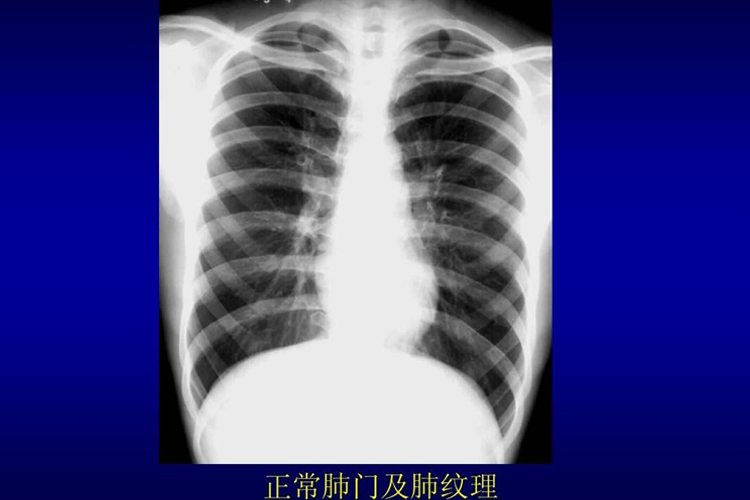

正常肺组织和肺部纤维化的区别通过影像学检查可明确,正常肺部结构的轮廓清晰,无扭曲变形,而肺部纤维化可见网格状阴影和蜂窝影。

而正常的肺部影像学检查无上述表现,可见到轮廓清晰的结构,两侧肺野的透明度相似,肺纹理分布均匀、无扭曲变形。